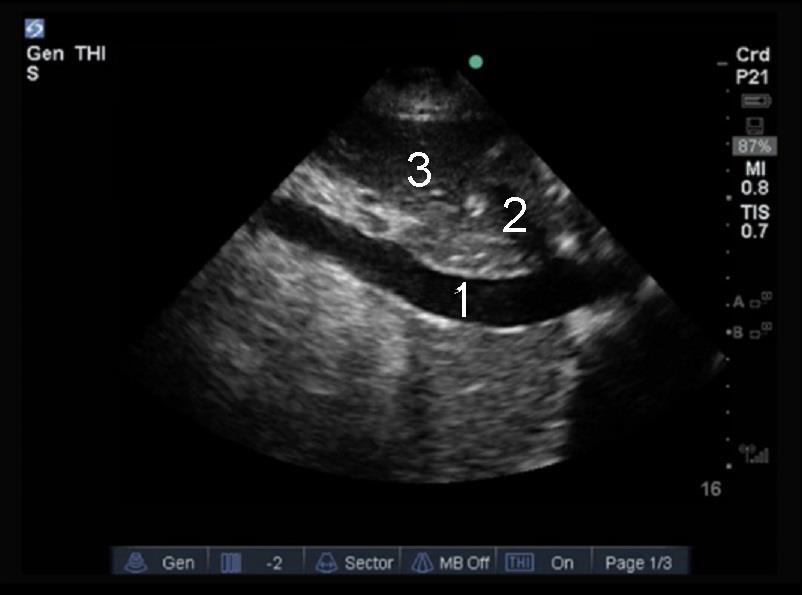

Clip vidéo - Échographie cardiaque - Veine cave inférieure (VCI), Coupe sagittale

1. Veine cave inférieure (VCI)

2. Veine hépatique (HV)

3. Foie